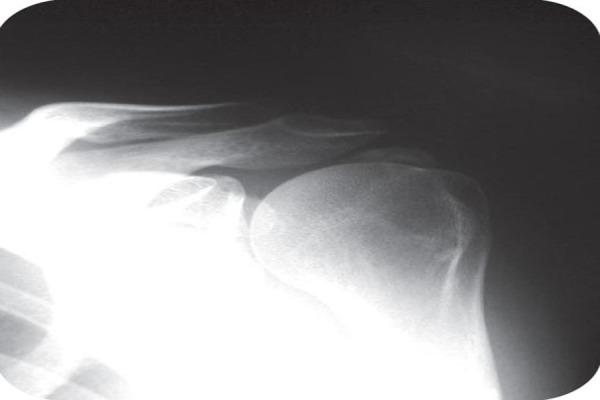

The ischiogluteal bursa is an inconstant anatomical finding located between the ischial tuberosity and the gluteus maximus. Ischiogluteal bursitis is a rare disorder.

We report the case of a 43-year-old female patient with bilateral calcifying ischiogluteal bursitis. The patient had no relevant medical history of systemic illness or major trauma to the buttock. After aspiration of both ischiogluteal bursitis which delievered calcareous deposits and instillation of a mixture of 1cc betamethasone (6 mg) and 4 cc of 1% lidocaine the patient was out of any complaints.

Calcifying ischiogluteal bursitis is a rare entity but easily diagnosed on radiographs. Aspiration and local steroid instillation give good relief from symptoms.